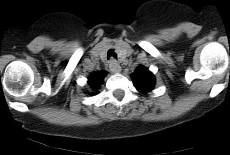

问题 男,68岁,呼吸困难、轻度吞咽困难3月余,请结合CT,选择最可能的诊断 ( )

选项 A.气管乳头状瘤 B.气管脓肿 C.气管炎性假瘤 D.食管癌 E.甲状腺癌

答案 A